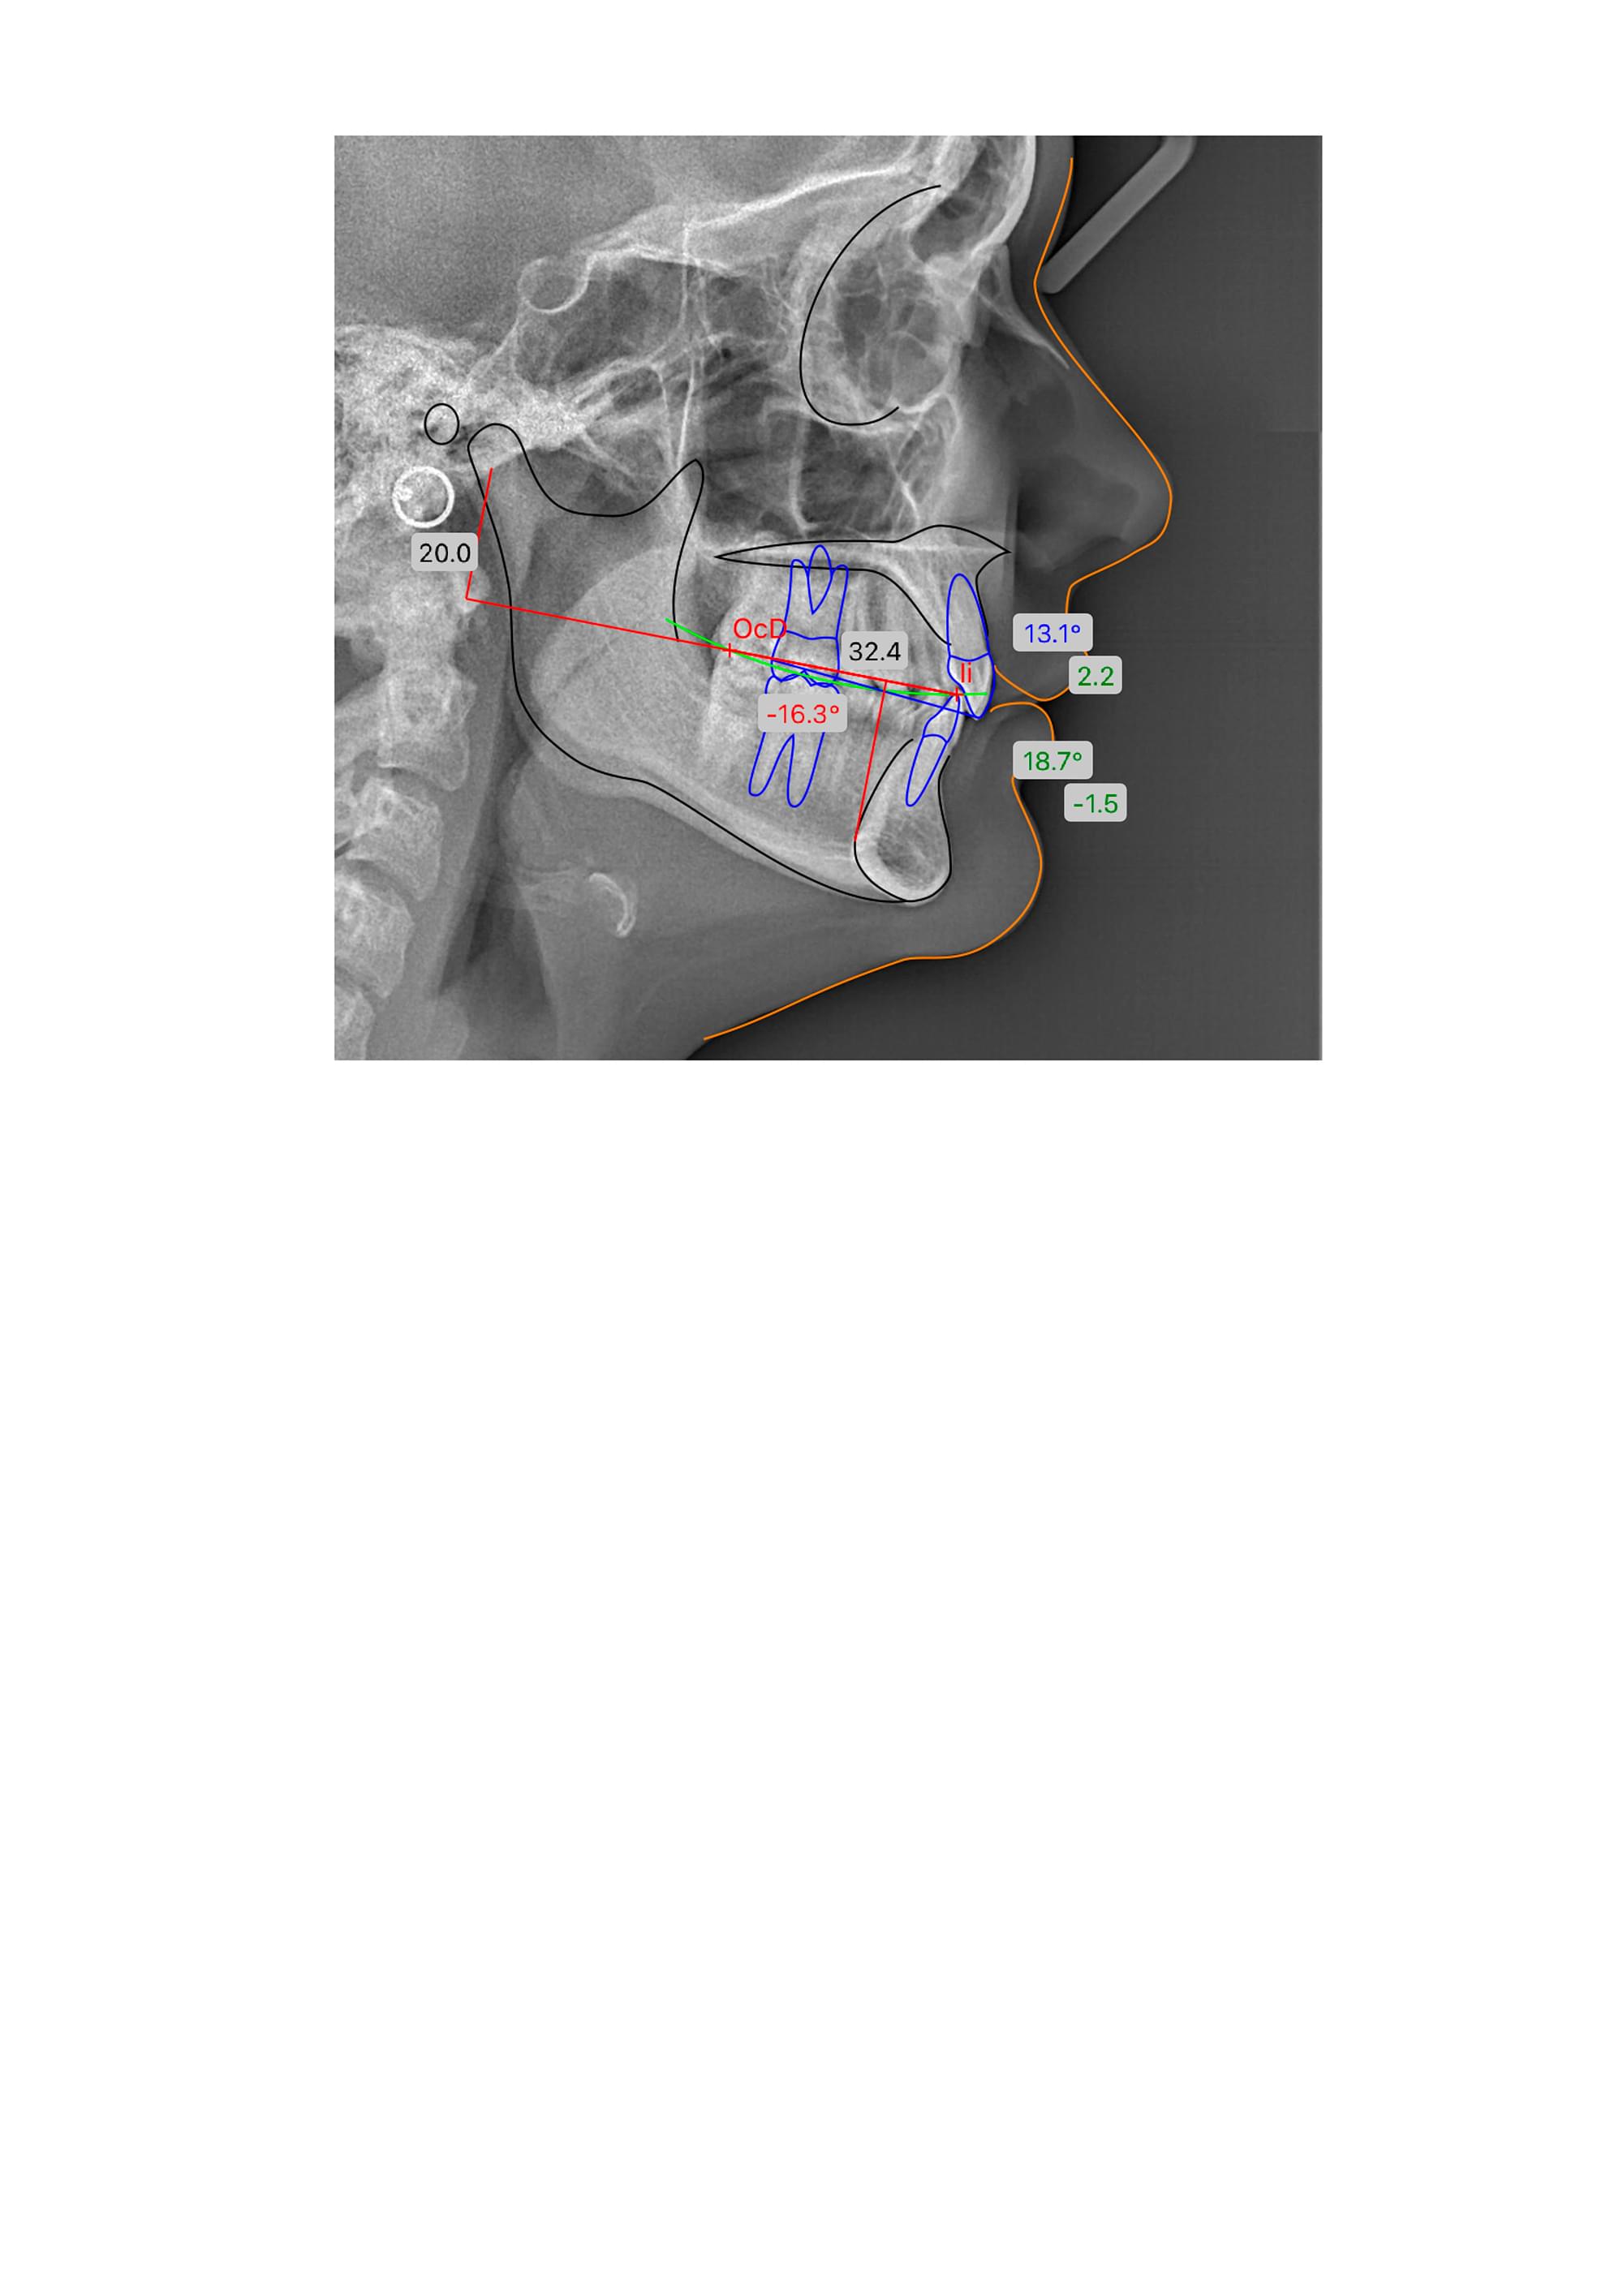

Це окрема діагностична послуга, під час якої лікар-діагност оцифровує знімок, розставляє анатомічні точки та вимірює кути і відстані між кістками черепа та зубами.

🔹 Індивідуальний план, а не шаблонний. Усі люди різні. Розрахунок показує ваш тип росту

(вертикальний чи горизонтальний), що критично важливо для вибору брекетів або апаратів.

🔹 Прогноз результату. Цифровий аналіз дозволяє змоделювати, як рухатимуться зуби. Це

страхує від помилок і непередбачуваних результатів через рік носіння брекетів.